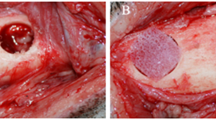

BCPSCs were obtained from two female Sprague–Dawley rats aged 4 weeks. After sacrifice, using CO2 inhalation under aseptic conditions, the four BFPs were accessed through a vestibular horizontal incision distal to the maxillary second molar (Fig. 1A). Once located (Fig. 1B), they were removed by gentle, careful soft tissue dissection (Fig. 1C), and were introduced into a sterile Eppendorf tube with 1.5 mL of sterile phosphate-buffered saline (PBS) to which antibiotic (1 mg/mL of streptomycin and penicillin) (Sigma-Aldrich Chemistry, S.A., Madrid, Spain), and antifungal (1 mg/mL of fungizone) (Sigma-Aldrich Chemistry, S.A., Madrid, Spain) (Fig. 1D) were added.

Creating and filling the CSBDs in the mandibular symphysis. A A 10-mm-long incision (crescent-shaped curving caudally) was made at the lower edge of the mandible. B Filling CSBDs (2 × 4 mm) in an osteoporotic animal with 10 mg porous BC cultured with 7.5 × 105 BFPSCs with osteogenic induction. C Suturing the periosteum. D Suturing the skin

The CSBDs in the mandibular symphyses of eight animals in each group were filled with 10 mg porous BC Osteosynt@ (Eincobio Biomaterial Ltd., Belo Horizonte, MG, Brazil) (60% HA/40% β-TCP), while the CSBDs in the remaining eight animals were filled with 10 mg porous BC Osteosynt@ (Eincobio Biomaterial Ltd., Belo Horizonte, MG, Brazil) cultured with 7.5 × 105 BFPSCs with osteogenic induction (Fig. 2B), according to the amount of BC and the number of BFPSCs proposed by Yagyuu et al. [31]. Planes were closed using 4/0 absorbable sutures (Laboratories Normon S.A., Madrid, Spain) to suture the periosteum (Fig. 2C) and the skin was sutured with braided silk (Lorca Marín S.A., Murcia, Spain) (Fig. 2D).